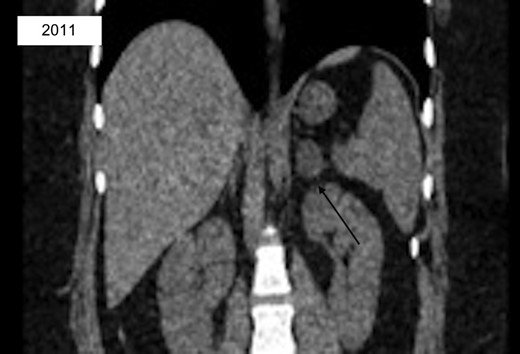

A 27-year-old Caucasian female with a past medical history significant for untreated hypertension, irritable bowel syndrome, hidradenitis, and ovarian cysts presented to the emergency department for evaluation of a three-day history of left flank pain. She had a prior CT scan seven years prior at which time a 2.7 × 2.1 cm left adrenal lesion, consistent with an adenoma, was found (Fig. 1). At recent presentation, non-contrast CT scan of the abdomen and pelvis was performed, demonstrating a 5.6 × 3.7 × 4.0 cm mass contiguous with the left adrenal gland and splenic artery (Fig. 2). She was ultimately discharged home with recommendation for further outpatient workup. Subsequent CT of the abdomen and pelvis with IV contrast revealed a 5.0 × 6.2 cm left adrenal mass. Portal phase density was 67 HU with washout seen at 15 minutes with HU of 42. MRI of the abdomen with adrenal protocol was then performed, depicting a 4.7 × 5.9 cm enhancing left adrenal mass with a differential diagnosis of pheochromocytoma, adrenal carcinoma, and metastatic disease. Biochemical workup was unremarkable aside from an elevated total/free testosterone of 124 ng/dl and 17.2 pg/ml. However, a diagnosis of polycystic ovarian syndrome was discussed with her in the past. The patient was then seen in the surgical oncology clinic at which time she complained of persistent left flank pain with no abnormal findings on physical examination. Surgical resection was recommended and patient underwent a robotic assisted laparoscopic left adrenalectomy. She had an uncomplicated post-operative course and was discharged home the following day. Surgical pathology revealed a high grade ACC measuring 8.4 cm in greatest dimension. There was invasion into the adrenal capsule and presence of small vessel lymphovascular invasion. Surgical margins were uninvolved with distance to closest radial margin of one mm. Immunostain showed significantly elevated Ki-67 labeling index up to 30% in focal areas of the tumor. The tumor also showed focal mitotic activity ranging from 0-4 mitoses/HPF, resulting in a diagnosis of high grade ACC. This case was discussed at a multidisciplinary meeting and adjuvant treatment was recommended. She then received external beam radiation to the left adrenal bed with a total dose of 5040 cGy at 180 cGy/F. She established care with medical oncology and was started on Mitotane with a goal dose of 6000 mg/day and goal level of 14-20 mcg/mL.

CT abd/pelvis revealing interval enlargement with heterogeneous density, now 5.0 × 6.2 cm with eccentric hyperdense region.